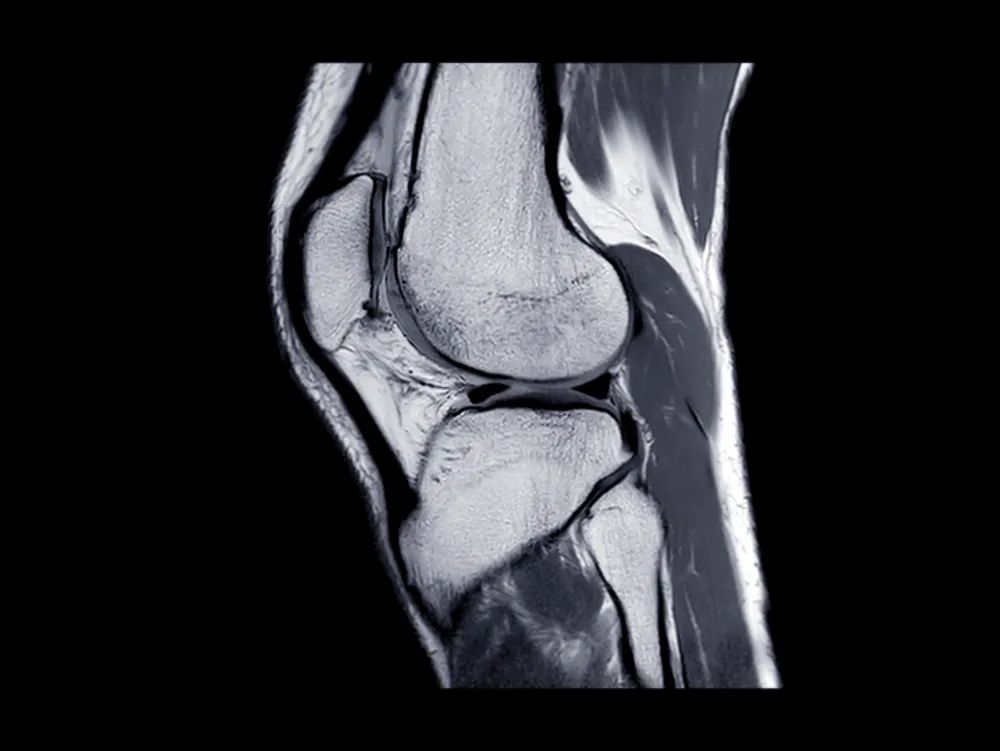

髌骨骨折只占全身骨折的 1%,治疗方式的选择和并发症的防治尤其要注意,急诊来了髌骨骨折患者,你怎么处理?髌骨是人体最大的籽骨,位于膝关节伸膝装置内。解剖特点包括近端宽大的基底和关节外的远侧尖端,前面位于关节外,后面为关节面。股直肌和股中间肌止于髌骨基底部,股内侧肌和股外侧肌止于髌骨的两侧。髌腱起于髌骨尖端,止于胫骨结节。髌骨骨折约占所有骨折的 1%,主要由直接暴力造成,如跌倒时跪地或膝关节屈曲时受到打击。典型的体征包括关节肿胀、压痛、伸膝功能部分或完全丧失。除以主诉和典型体征外,膝关节 X 线片也是必不可少的一项辅助检查,以膝关节正侧位 X 线片最常见,如果怀疑纵向骨折,膝关节屈曲 45° 时髌骨 30° 切位片可以辅助诊断。对于骨折不愈合、畸形愈合所致的关节面不平整以及髌股关节对应关系不良可采用 CT 检查。MRI 有助于诊断软骨缺损和损伤。34-B 型(部分关节内骨折,伸膝装置完整,如纵行骨折)髌骨下极骨折袢钢板结合克氏针、张力带固定 图源:作者提供

拉力螺钉加张力带钢丝固定或经胫骨结节绕髌环扎;经骨缝合撕裂的肌腱加髌骨和胫骨结节间钢丝环绕以加固缝合;袢钢板固定。无移位采用非手术治疗;移位并且单纯骨折采用横向拉力螺钉固定,骨质疏松患者需加环扎固定;对于多骨折块(星状)则采用髌骨环扎加张力带进行固定。克氏针加张力带钢丝;有第三个骨折块则采用拉力螺钉或克氏针加张力带钢丝固定;对于 4 个或 4 个以上的骨折块采用克氏针加螺钉加张力带钢丝进行固定;对于严重粉碎和软骨面广泛破坏的髌骨骨折,髌骨部分或完全切除也是一种可行的办法。